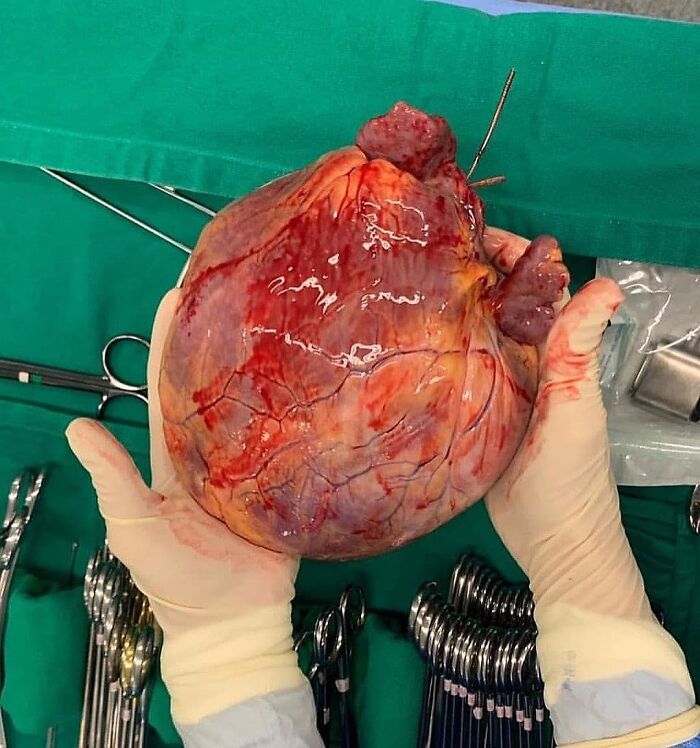

Pediatric Heart Transplantation

A Mega-Size Globular Heart!! This Very Large Heart Has A Globoid Shape Because All Of The Chambers Are Dilated. It Felt Very Flabby, And The Myocardium Was Poorly Contractile